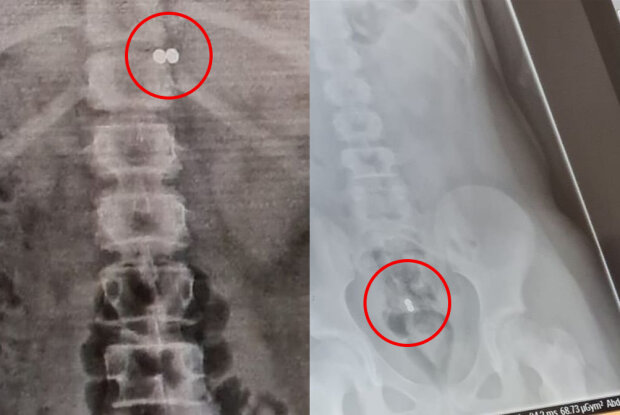

Керри рассказала, что в больнице рентген показал магниты на уровне диафрагмы, но уже на следующий день, когда мама с дочкой вернулись к специалисту, детальки были в прямой кишке. Пока операция не прошла, но врачи уже готовятся к её проведению, ведь два настолько сильных магнита могут сильно навредить юному организму.